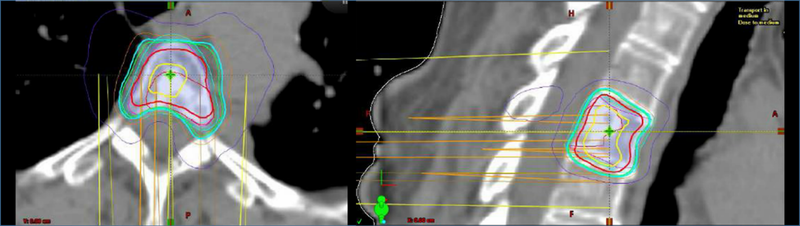

Traditional conventional radiotherapy techniques (either 2D or 3D conformal radiotherapy) have been used in patients with osseous metastatic disease, including spine metastases (Fig. 1). Stereotactic radiosurgery (SRS) techniques, initially developed for patients with intracranial metastasis, have increasingly been tested in patients with spine metastasis with encouraging results (Fig. 2).

Figure 2